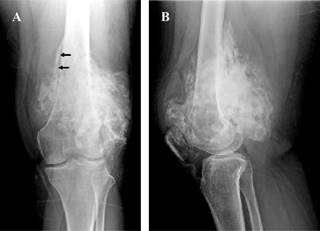

Anteroposterior and lateral radiographs of the left knee showed an exophytic and lobulated bone tumor attached mainly to the posterior surface of the distal third of the diaphysis and distal femoral metaphysis. The tumor presented central dense ossification and a thin, radiolucent zone between the tumor and the underlying bone (Figure 1).

Figure 1: Anteroposterior radiography (A) and lateral (B) of the left knee. Lobulated and exophytic bone tumor with central dense ossification, adjacent mainly to the posterior surface of the distal third of the diaphysis and distal femoral metaphysis. Presence of radiolucent cleavage (arrows) that separates the tumor and the adjacent normal cortex (sign of the rope) which corresponds histologically to the periosteum interposed between the cortex and the tumor mass.